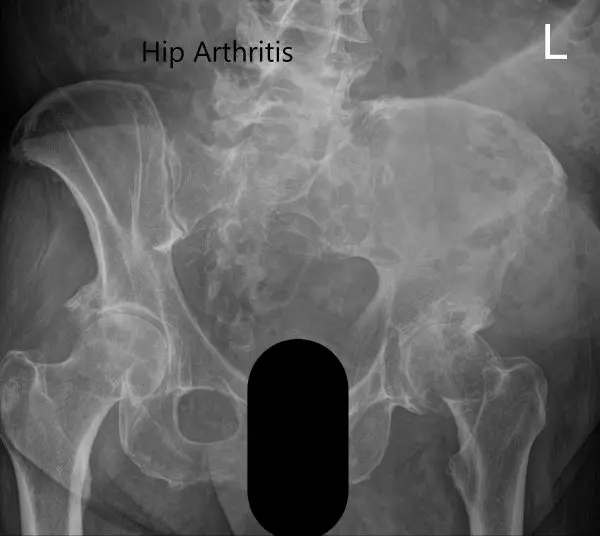

Preoperative X-ray showing the Judet view of the pelvis.